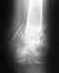

Здравствуйте. 2 апреля я сломала б/берцовую кость. 12 сделали зимо со статическим блокированием, но поставили не те спицы котые мы купили.

Поставили наши, а мы брали импортные.Обещали что пойду через месяц, но прошло уже 3 месяца, а у меня не идет сращение кости. Не могли бы вы сказать почему? еще мне во время операции задели нерв, который идет к большому пальцу, из-за этого он не работает.Я ходила на электрофорез с прозерином не помогло. Электоростимуляця не пошла-очень больно. Скажите пожалуйста возможно ли ускорить сращение и как то восстанивить нерв? спасибо

Верятно, то, что использовали другой стержень, было обусловлено тем, что во время операции купленный не подошел по размеру. Но сделано все неплохо и с этим стержнем.

Если гвоздь был заперт статически, также уже пора его отпереть, убрав один винт вверху - это сделано?

Если сращение не наступит через 2-3 мес. после динамизации гвоздя и ходьбы с полной нагрузкой (это крайне редко, но бывает), оптимально будет заменить стержень на другой, большего диаметра. Как правило, это решает проблему.